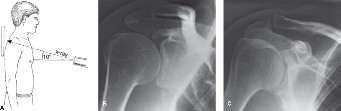

A 55-year-old, right-hand-dominant female presents with right shoulder pain for 6 months. She localizes the p…